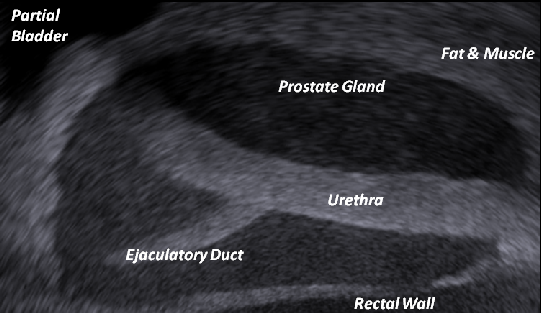

Prostate phantom, Urethra and Ejaculatory Duct -Exact 3D shape and siz

• Exact Ultrasound echogenicity as seen by surgeons during OR procedure.